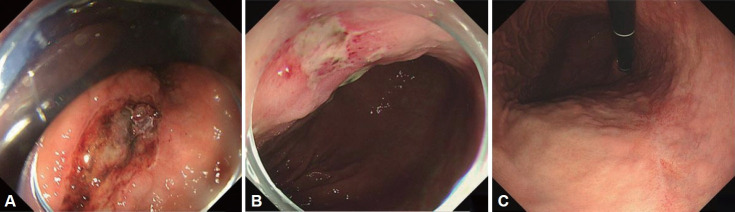

脂肪来源的干细胞因其易于大量获得而备受关注。然而,对其副作用的担忧也被提出。在干细胞治疗过程中,如果医疗器械灭菌不完全和/或细胞加工和培养过程中的卫生不理想,可能会发生分枝杆菌感染。一般来说,分枝杆菌感染最常表现为肺炎;然而,骨骼、淋巴结、皮肤、软组织和血液的感染也会发生。分枝杆菌菌血症的发生相对频繁,但由于干细胞治疗和随后的分枝杆菌菌血症引起胃溃疡的病例尚未报道。在此,我们报告了一位75岁的男性,他在脂肪来源的干细胞注射后出现了分枝杆菌菌血症和胃溃疡。本病例报告提高了人们对脓肿分枝杆菌复合体菌血症和随后的胃溃疡出血的可能性的认识,这是干细胞治疗的一种罕见并发症。

Adipose-derived stem cells are gaining attention because they are easily obtained in large quantities. However, concerns about side effects of their use have also been raised. Mycobacterial infections can develop during stem cell treatment in the event of incomplete medical device sterilization and/or suboptimal hygiene during cell processing and culture. In general, mycobacterial infections most frequently manifest as pneumonia; however, infections of the bones, lymph nodes, skin, soft tissues, and blood also occur. Mycobacterial bacteremia occurs relatively frequently, but cases of gastric ulcers induced as a complication of stem cell treatment and subsequent mycobacterial bacteremia have not been reported. Herein, we report a 75-year-old man who developed mycobacterial bacteremia and gastric ulcers following adipose-derived stem cell injection. This case report raises awareness of the possibility of Mycobacterium abscessus complex bacteremia and subsequent gastric ulcer bleeding-a rare complication of stem cell therapy.